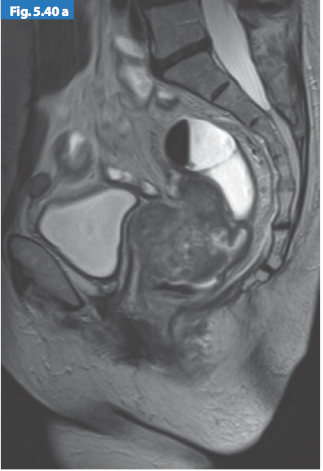

- T4: được chia T4a: khối u trực tiếp xâm lấn thanh mạc hoặc cân mạc treo trực tràng. T4b: khối u xâm lấn trực tiếp hoặc dính vào các tạng, cơ quan khác.

Hình 6. Sự giảm tín hiệu của khối u xâm lấn vào thành sau âm đạo

Hình 7. Khối u giai đoạn T4 trên hình ảnh T2w axial xâm lấn lá phúc mạc và cổ tử cung

Hình 8. Khối u giai đoạn T4 trên hình ảnh T2w sagittal xâm lấn âm đạo

và cân mạc treo trực tràng